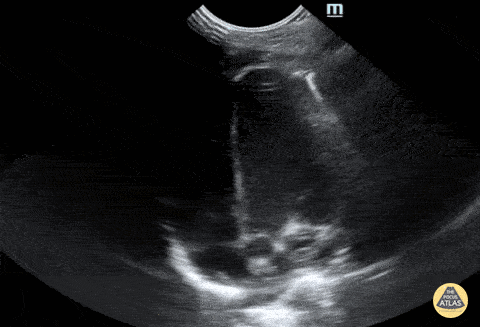

Normal neonatal apical 4 chamber. Contributor: Jaron Smith, MD, Phoenix Children's Hospital

View: Unspecified Parasternal Long Axis Parasternal Short Axis Apical Four-Chamber Subcostal Four-Chamber Subcostal Inferior Vena Cava Right Upper Quadrant Left Upper Quadrant Suprapubic Longitudinal Suprapubic Transverse Subxiphoid Anterior Thoracic Phrenic